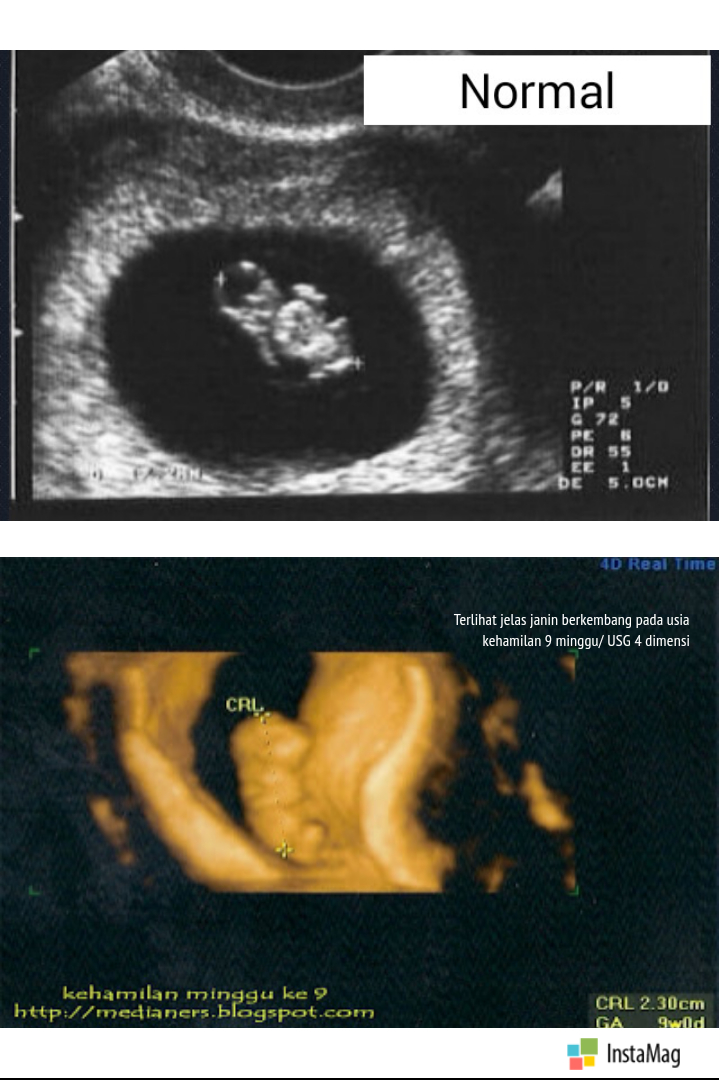

Blighted Ovum, Kehamilan Tanpa Janin - Medianers

Blighted Ovum, Kehamilan Tanpa Janin - Medianers

Blighted Ovum, Kehamilan Tanpa Janin - Medianers

Blighted Ovum, Kehamilan Tanpa Janin - Medianers

Mengenal Kehamilan Kosong atau Blighted Ovum (BO) - Bidanku.com

Mengenal Kehamilan Kosong atau Blighted Ovum (BO) - Bidanku.com